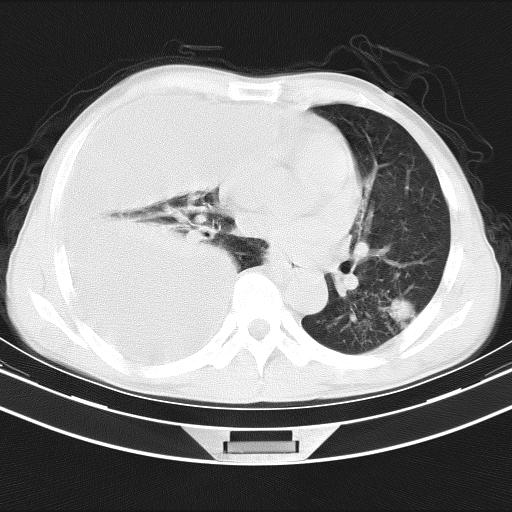

男性,44岁,结核病史多年。现胸闷气短,咳嗽,偶咳血。

右侧胸腔积液

右肺下叶不张

双肺多发结节影最分空洞形成考虑占位不除外结核

双肺陈旧性病变

1、右侧大量胸腔积液伴右肺压缩性膨胀不全,建议抽液治疗后复查 2、两肺继发性tb伴空洞形成。

1)两肺继发性肺结核伴空洞形成,左肺多发性结核球。2)右侧大量胸腔积液伴右肺部分膨胀不全。3)纵隔淋巴结肿大。